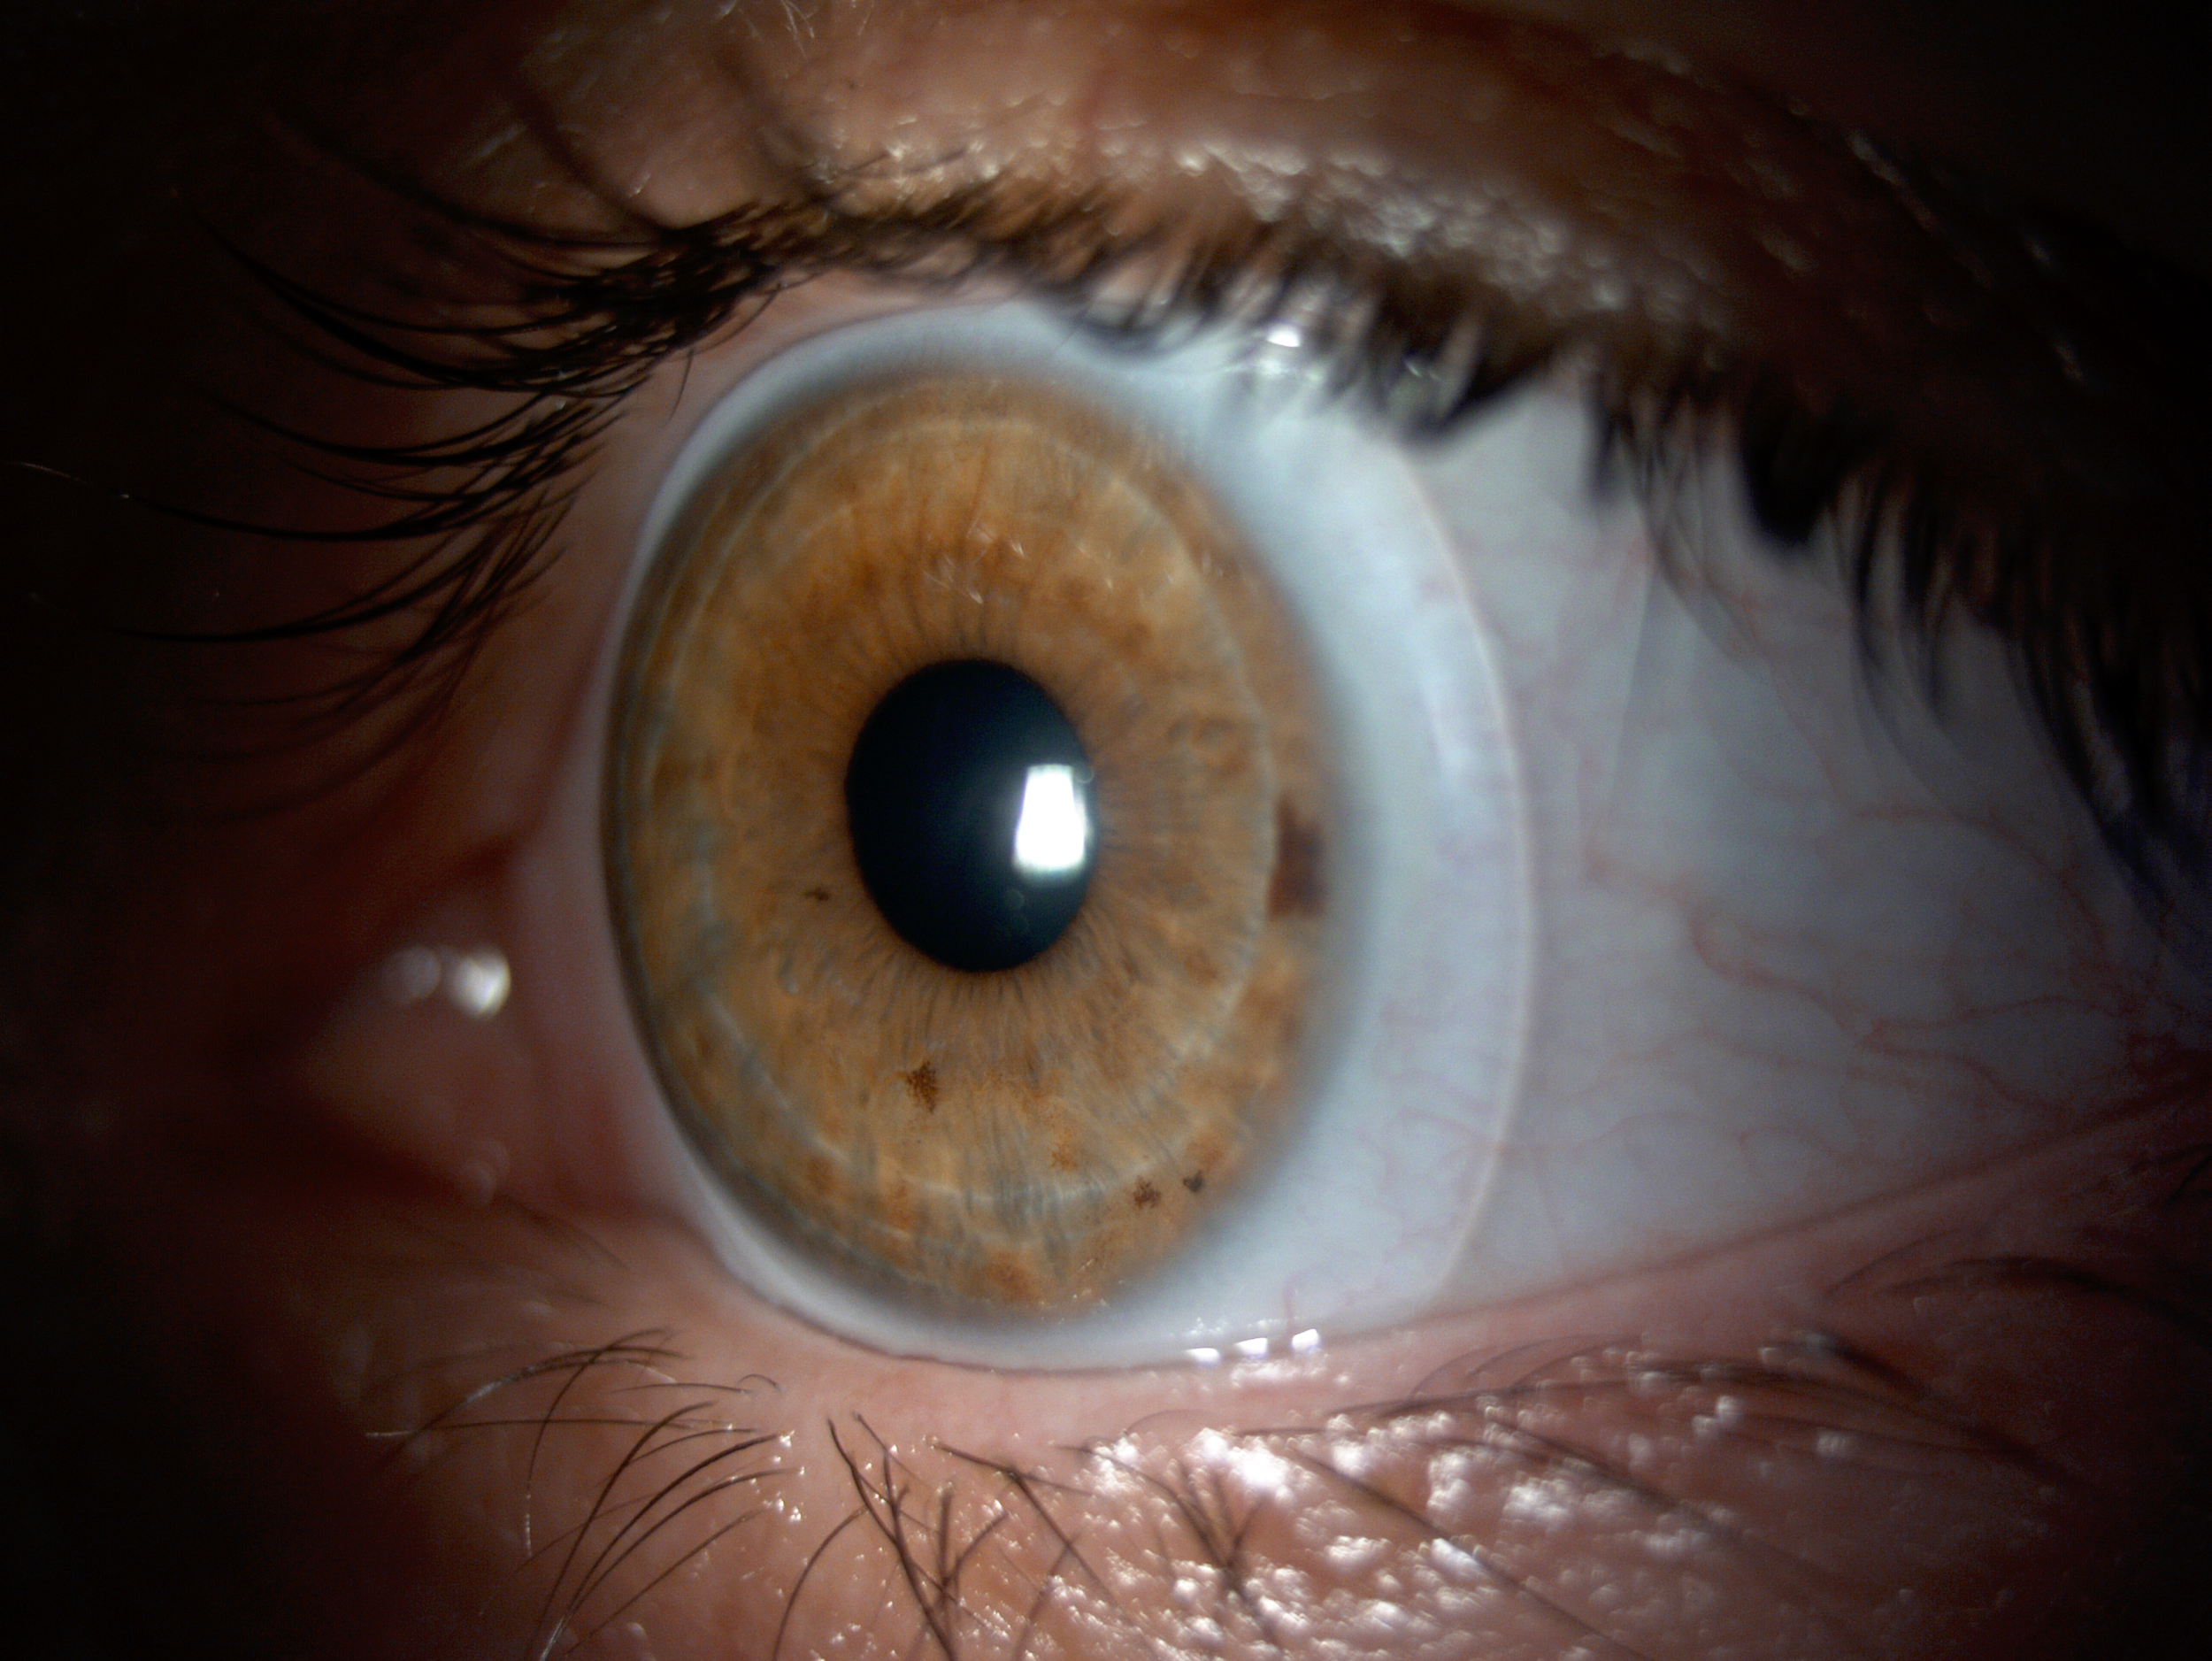

Scleral lenses are large diameter gas-permeable contact lens devices.

Rather than sitting directly on the eye like a traditional soft lens, scleral lenses only touch the sclera (the white part of the eye) and vault entirely over the cornea (the front of your eye - a clear layer of tissue that covers your iris, pupil and lens). This vault - the space between the contact lens and your cornea - is filled with fluid and creates a new, perfect focusing surface.

By vaulting over the eye with fluid, we are able to manage complicated eye conditions such as astigmatism, keratoconus, corneal transplants, severe dry eye, corneal scarring, LASIK complications and more. These lenses can be life changing.